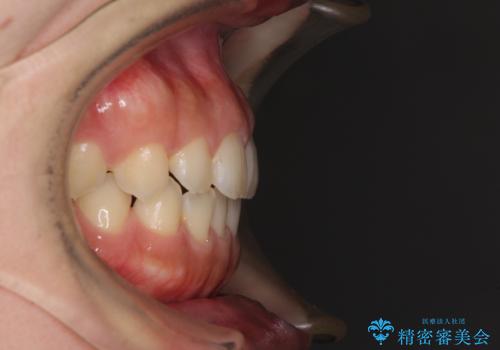

気になる隙間の再矯正 前歯をインビザライン・ライトで改善

- 後戻りによる上下前歯の隙間を気にして来院された患者様です。

歯列不正はそれほど大きくなかったため、インビザライン・ライトを用いて矯正治療を行うこととしました。

無理のないペースで治療を進め、9ヶ月で終えることができました。